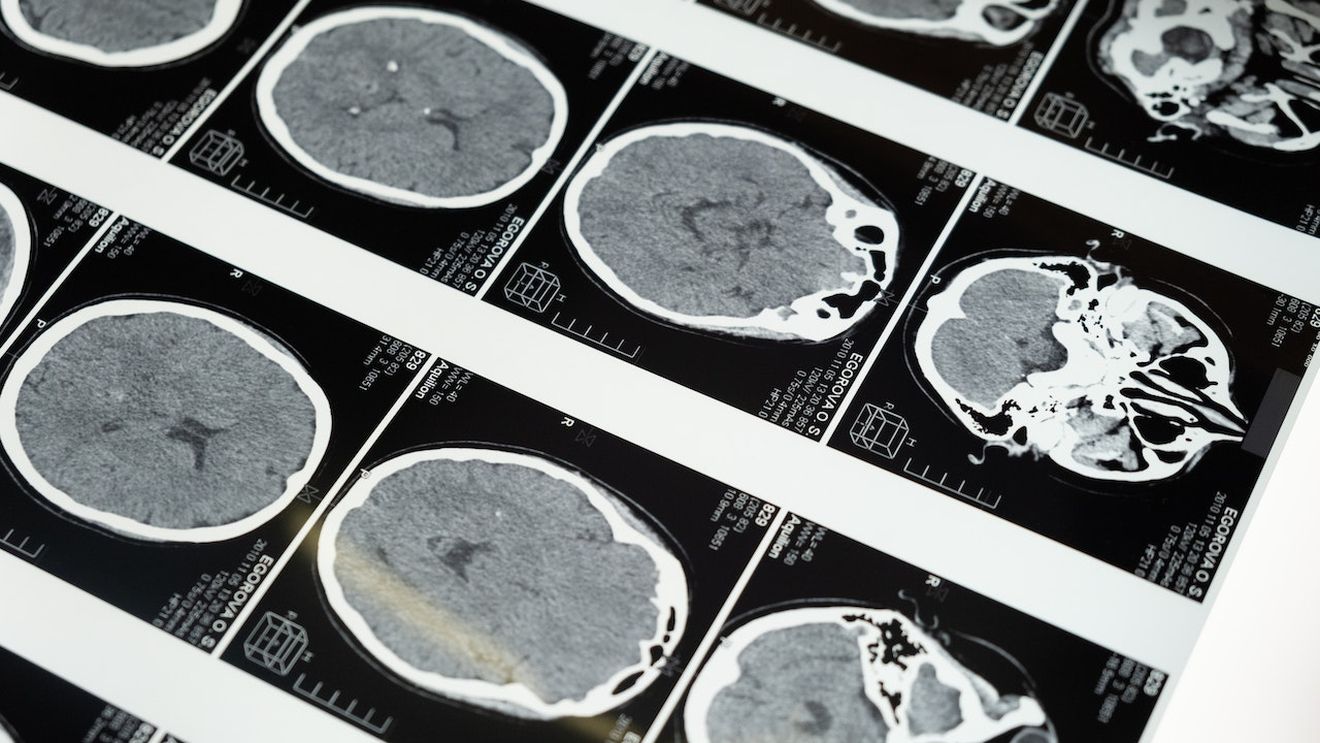

Un dispozitiv sofisticat, un stimulator conectat la doi electrozi plasați în nucleele profunde ale creierului, a fost introdus în pieptul unui pacient în vârstă de 66 de ani: nu numai că trimite stimuli electrici în anumite zone ale creierului, dar înregistrează în timp real și activitatea motorie, pentru a optimiza setul de terapie.

Stimularea blochează, de fapt, semnalele care cauzează simptomele motorii invalidante. La Irccs din Bellaria, echipa multidisciplinară formată din neurologi, neuroradiologi, fiziatri, logopedici, neuropsihologi, ingineri de analiză a mersului, neurochirurgi și anesteziști dedicată neurostimulării oferă pacienților cu Parkinson terapii din ce în ce mai personalizate datorită inovației tehnologice.